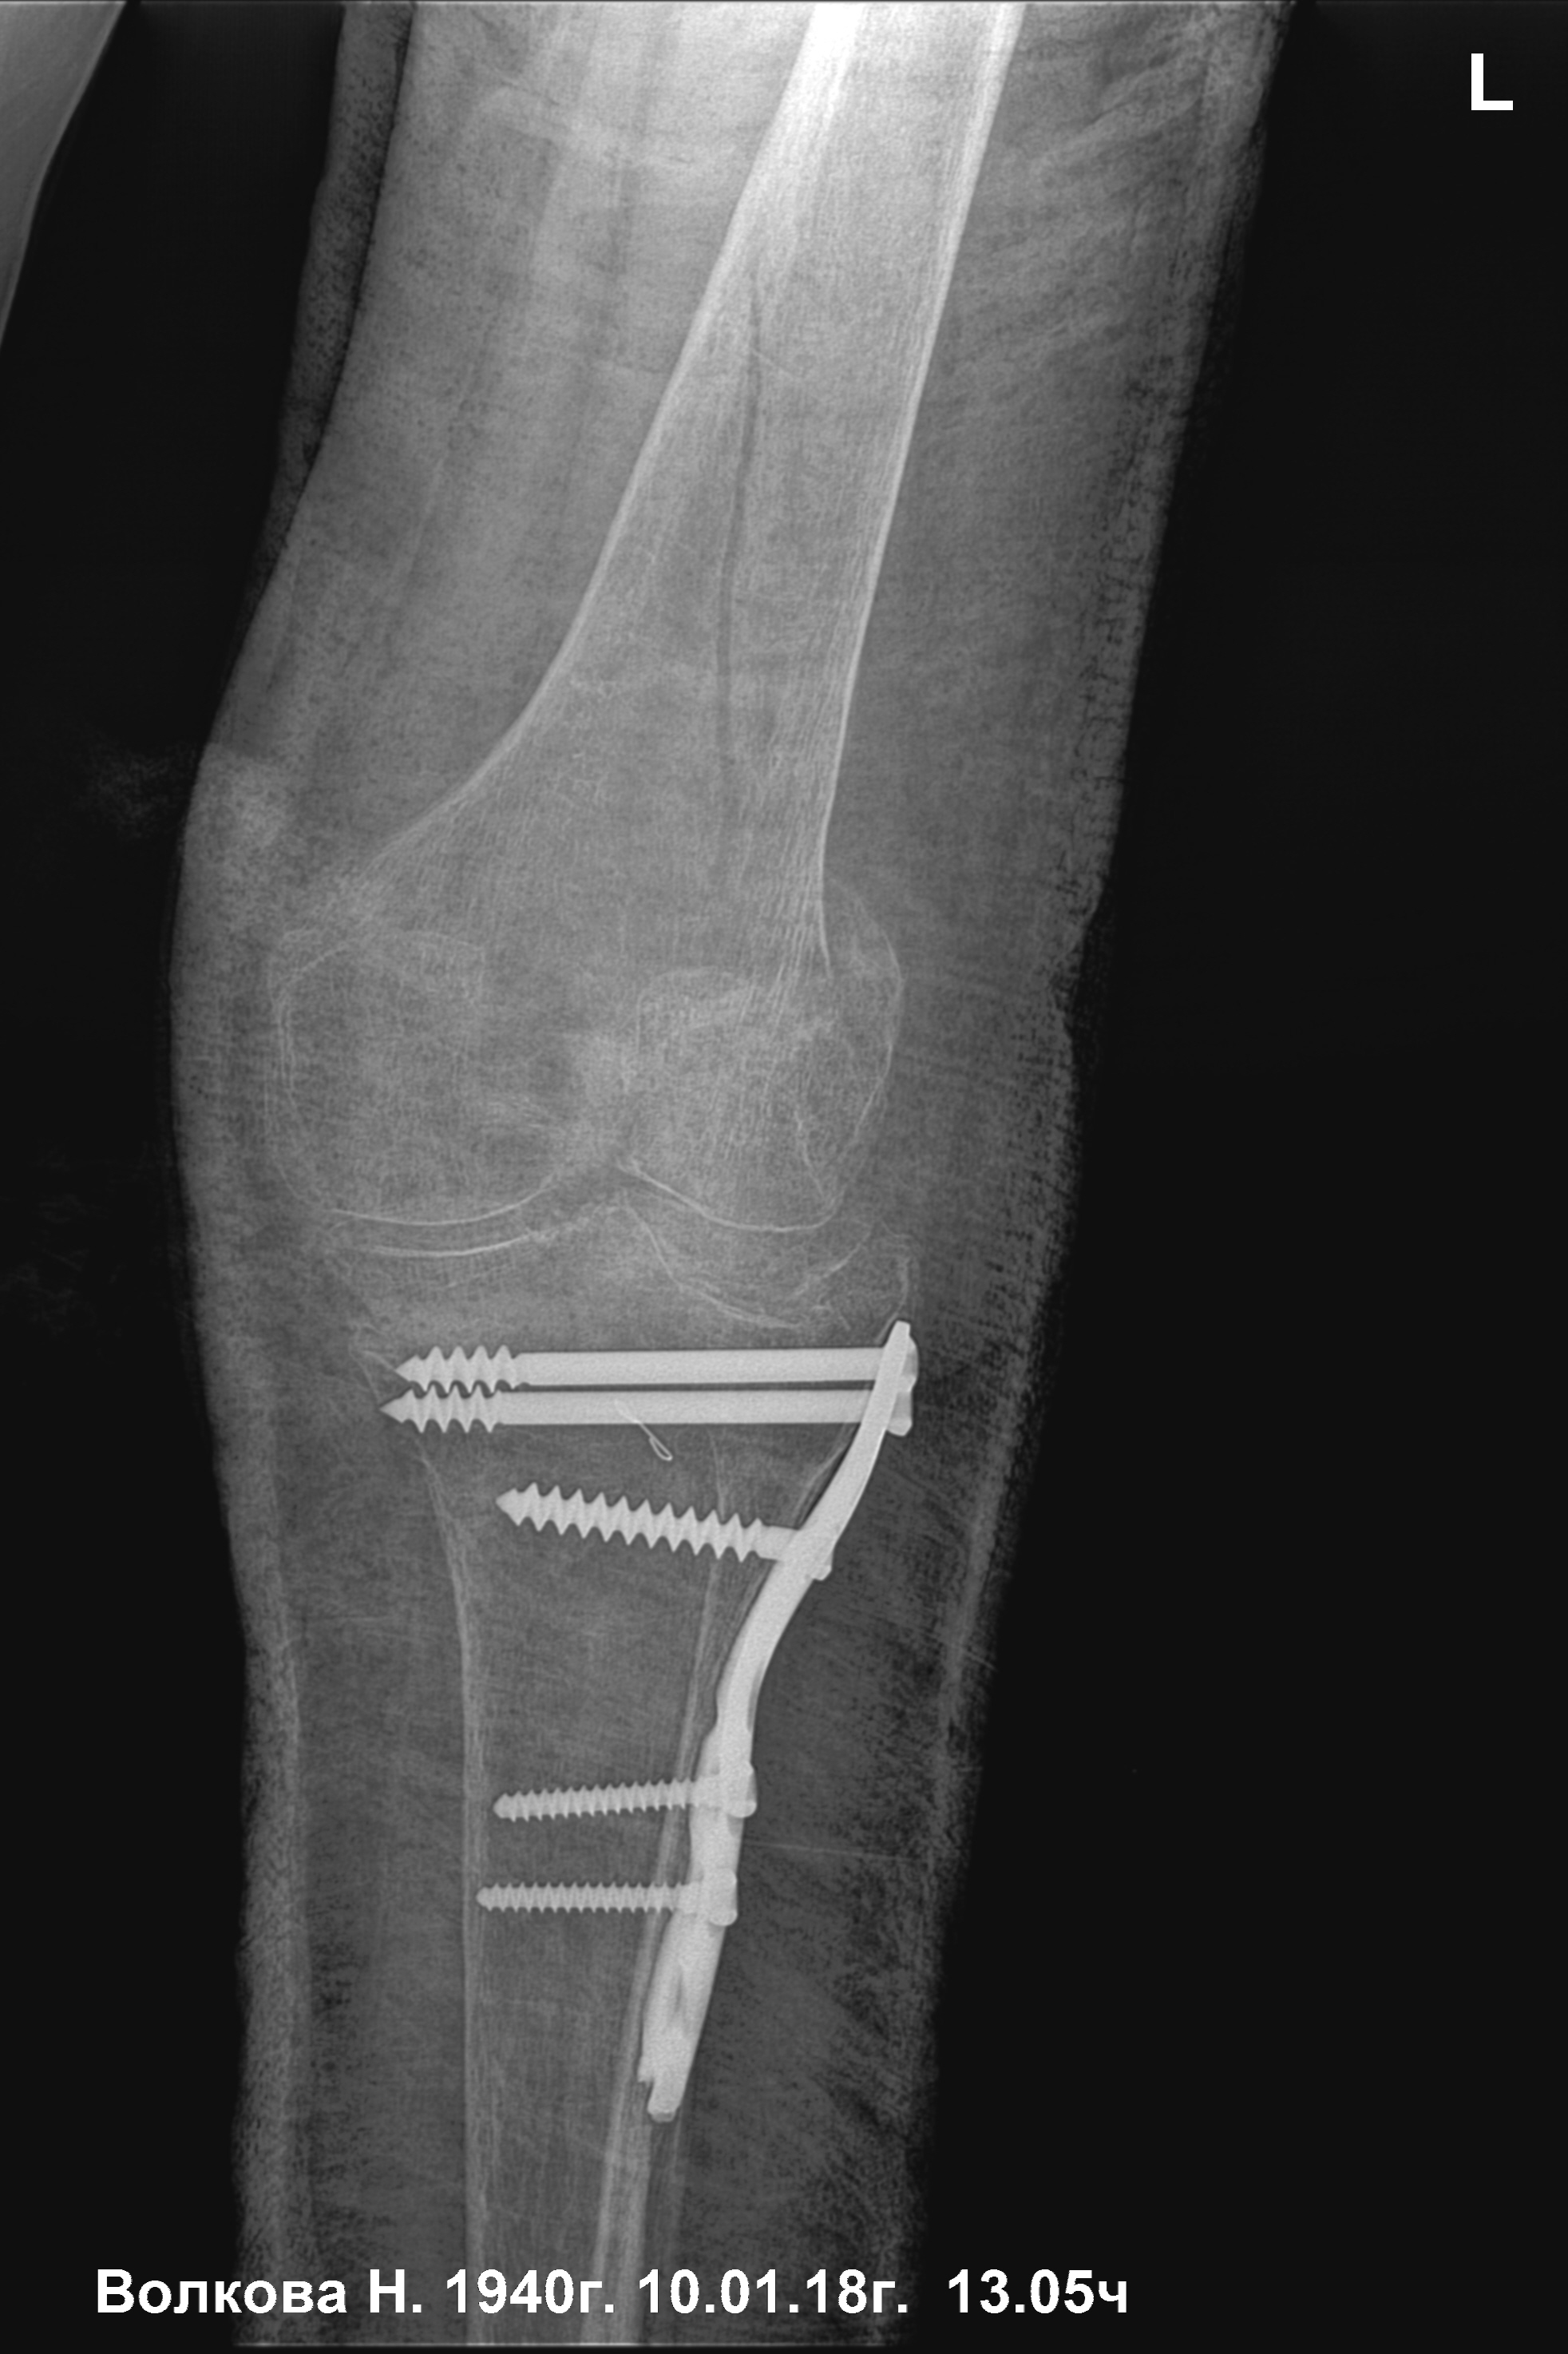

Re: Сросшийся чрезвертельный и перелом н\3 бедра

нижняя треть